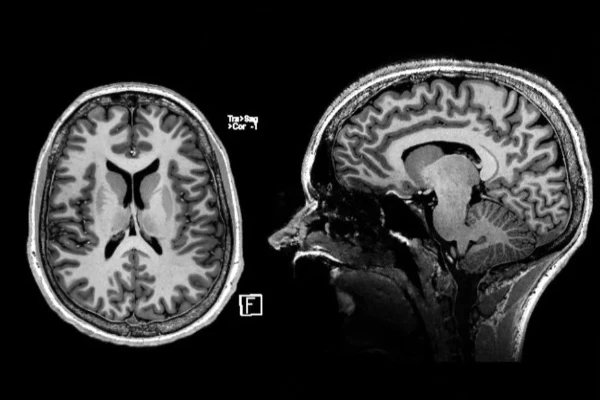

In 2019 the Translational Imaging Center (TIC) has been established at the Campus of the Swiss Institute for Translational and Entrepreneurial Medicine (sitem-insel AG). Our mission is to enable translational imaging research ranging from molecular chemistry and physics to applied human-oriented research. We employ advanced magnetic resonance imaging closely linked to the clinical environment and the research at the University of Bern and the University Hospital Bern (Inselspital). The heart of our center is an innovative 7 Tesla UHF MRI designed specifically for clinical operation. This FDA and CE-labelled UHF-technology has revolutionized diagnostic imaging in many domains and serves as a diagnostic center for specialized medical indications. Further, with the ongoing paradigm shift from cohorts to personalized medicine, diagnostic imaging and disease monitoring supports the identification of novel biomarkers, metabolomic and radiomic analyses. Through this translational approach we further envision the development of products in the field of medical technology, also offering a unique entrepreneurial platform.

MRI technology continues to develop rapidly, and increasingly specialized applications have opened up an environment for comprehensive synergistic research areas consisting of life science, medicine and other basic research, including magnetic resonance methods, system biology and biomedical engineering. Working groups from the University Hospital Bern (Inselspital) and the University of Bern have joined forces to form an MRI research consortium with the goal to develop an integrative platform for translational research and education. The platform constitutes one of the core enabling facilities at sitem-insel and aims at leveraging the research from the cellular level up to clinical research. Close collaboration with our industry partners enables the development of novel MRI methods and applications and their translation into advanced and personalized patient care.

Inselspital Bern has pioneered the use of 7-Tesla Magnetic Resonance Imaging (7T-MRI), a cutting-edge tool enhancing diagnostic capabilities in neurology. Dr. Piotr Radojewski from the University Institute for Diagnostic and Interventional Neuroradiology elaborates on its transformative potential in an interview. The ultrahigh-field 7T-MRI provides unparalleled imaging resolution, unveiling subtle brain structures and processes previously undetectable. Its applications are extensive, from detecting minor anomalies to evaluating complex conditions like epilepsy, multiple sclerosis (MS), and cerebrovascular diseases. For instance, 7T-MRI allowed the accurate diagnosis of a cortical dysplasia in an epilepsy patient, paving the way for targeted surgical intervention. Such advancements exemplify its superiority in identifying lesions invisible to standard 3T-MRI. In MS research, 7T-MRI has revealed cortical lesions and paramagnetic rim lesions, offering critical insights into disease progression and therapy optimization. Additionally, it is pivotal in diagnosing challenging conditions like CNS vasculitis and evaluating the safety of novel Alzheimer’s medications by identifying amyloid-related imaging abnormalities. Despite its promise, 7T-MRI is not yet a routine tool, given limited availability and ongoing evidence accumulation. Dr. Radojewski envisions its integration into standard clinical practice, akin to the historical trajectory of 3T-MRI, emphasizing the importance of collaborative feedback loops between clinicians, researchers, and technologists. This innovation underscores Inselspital’s commitment to leveraging technology for enhanced patient outcomes and sets a benchmark for the future of neuroimaging.